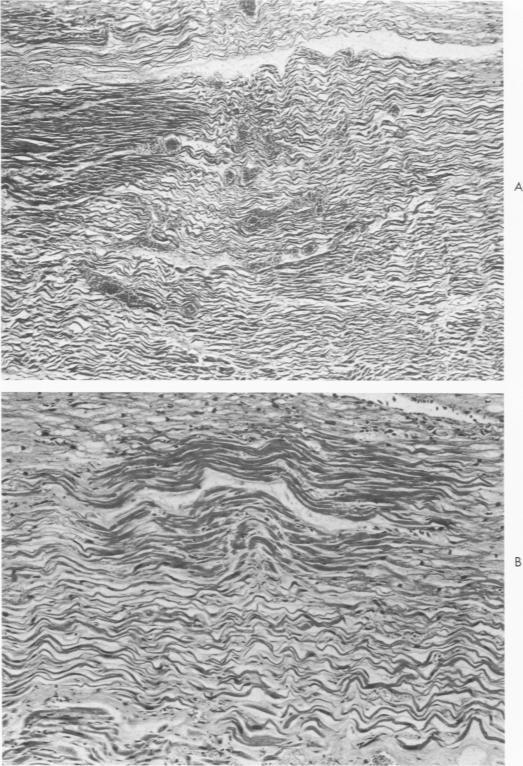

The histopathology of human myocardial infarcts is reviewed in a series of 46 cases ranging from sudden death to a clinical age of 3 days. A set of histopathologic features is described whereby the diagnosis of acute myocardial infarction can be made, even in cases of sudden death, on routine sections and even after considerable autolysis. This is primarily a stretching and waviness of the myocardial fibers, especially at the border of the infarcted area. Its mechanism is probably twofold: the rythmical pull exerted by the normal myocardium against the infarcted paralyzed area and the outward bulging of this area at every systole. On the basis of human material alone, it may be inferred that this pattern develops very rapidly: surely less than 1 hour and perhaps a few minutes after the local circulation has failed.

回顾了46例人类心肌梗死的组织病理学情况,这些病例涵盖了从猝死到临床病程3天的患者。描述了一组组织病理学特征,据此即使在猝死病例中,通过常规切片,甚至在经历相当程度的自溶后,也能够作出急性心肌梗死的诊断。这主要表现为心肌纤维的伸展和波纹状,特别是在梗死区域的边界处。其机制可能是双重的:正常心肌对梗死的麻痹区域施加的节律性牵拉,以及该区域在每次心脏收缩时向外膨出。仅基于人体材料就可以推断,这种形态发展非常迅速:肯定在局部循环停止后不到1小时,也许几分钟内就会出现。